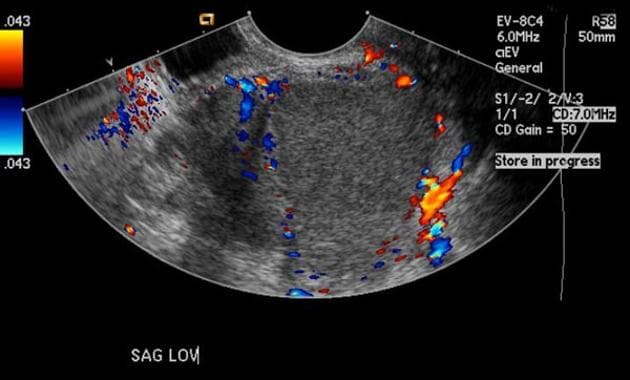

- Tổn thương dạng nang lớn ở vùng chậu bụng bên phải, trên cộng hưởng từ (MRI) tổn thương này tăng tín hiệu ở chuỗi xung T1 và T2, có vách ngăn nội tại.

- "U lạc nội mạc tử cung thường biểu hiện là các nang buồng trứng đơn hoặc đa ngăn, có tăng tín hiệu đồng nhất trên cả chuỗi xung T1 và T2 do chứa sản phẩm máu mạn tính."

- "Dấu hiệu chấm tối trên T2 (T2 shading) trong lòng nang là đặc điểm điển hình của u lạc nội mạc, do lắng đọng hemosiderin đậm đặc."

- "Vách ngăn nội tại và dày thành nang dạng nốt cho thấy tình trạng mạn tính hoặc nguy cơ chuyển ác, cần theo dõi sát."

U lạc nội mạc tử cung, còn gọi là 'nang sô cô la', là một dạng lạc nội mạc tử cung khi mô nội mạc tử cung lạc chỗ bám vào buồng trứng và xuất huyết theo chu kỳ. Trên cộng hưởng từ (MRI), u lạc nội mạc thường có tín hiệu tăng trên cả chuỗi T1 và T2 do chứa máu cũ. Hiện tượng 'mờ tín hiệu trên T2' (T2 shading) – khi tín hiệu giảm dần trên hình T2 – rất gợi ý cho chẩn đoán u lạc nội mạc. Các chẩn đoán phân biệt bao gồm nang buồng trứng xuất huyết, u nang tuyến mề và u tuyến nang nhầy. Tuy nhiên, tín hiệu T1 tăng rõ rệt và vách ngăn nội tại làm tăng khả năng u lạc nội mạc. Chẩn đoán chính xác rất quan trọng để định hướng điều trị, bao gồm điều trị nội tiết hoặc phẫu thuật cắt bỏ, đặc biệt ở bệnh nhân vô sinh hoặc đau vùng chậu mạn tính.